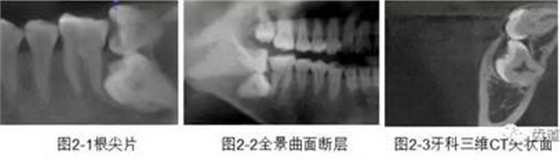

CBCT在牙體牙髓病科治療中,對(duì)牙根周圍的解剖關(guān)系、炎癥病變、囊腫等就能夠輕而易舉的進(jìn)行診斷。甚至與牙齒內(nèi)根管的數(shù)目、走向、分支等都能夠通過(guò)牙科CT進(jìn)行展示,使臨床醫(yī)生的根管治療不再是完全憑手感的“經(jīng)驗(yàn)科學(xué)”。通過(guò)CBCT,還可以對(duì)一些“久治不愈“的疑難病例進(jìn)行檢查和診斷,例如根縱列的診斷、根管內(nèi)異物的定位等,找準(zhǔn)了原因,結(jié)合先進(jìn)的治療技術(shù)因病施治,使疑難病例的治療變的輕松起來(lái)。

1、牙髓根管治療

1)根管治療中牙膠尖充填在CBCT中的影像

2)根管測(cè)量